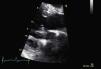

Para melhor esclarecimento da funcionalidade do aparelho valvular mitral, a paciente foi submetida a ETE (FC entre 120-150bpm) (Figuras 2 e 3) que revelou uma VM com anel de Carpentier e folhetos com aspecto degenerativo e redundante, apresentando boa abertura em diástole, mas evidenciando-se movimento anterior sistólico que condicionava obstrução do tracto de saída do ventrículo esquerdo pelo folheto anterior e insuficiência mitral grave (vena contracta=8mm). Vão estruturalmente tricúspide, com boa abertura e insuficiência ligeira. O apêndice auricular esquerdo encontrava-se livre de trombos.